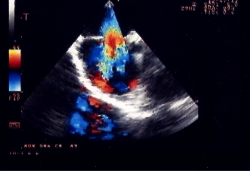

La procedura di impianto viene eseguita in anestesia generale con intubazione del paziente. Un ruolo essenziale, in tutte le fasi della procedura, è svolto dall’ecocardiografia transesofagea. Essa detta le indicazioni alla “fattibilità” (diametro del difetto, misura dei rims settali, ritorni venosi, anatomia atriale), guida l’operatore nel posizionamento della protesi a cavallo del difetto e nel successivo rilascio della stessa, permette una immediata valutazione del risultato (“tenuta” del device dopo rilascio, shunt residuo) (Figure 1, 3, 4). Dall’ottimale utilizzo e dall’esatta interpretazione dei dati forniti dall’ecocardiografia transesofagea dipende in larga parte la riuscita della procedura. Alcuni Autori riportano l’impiego di altri sistemi di monitoraggio durante la procedura quale ad esempio l’ecocardiografia intracavitaria (49). Quest’ultima consentirebbe di evitare l’uso dell’ecocardiografia transesofagea e quindi la necessità dell’intubazione.